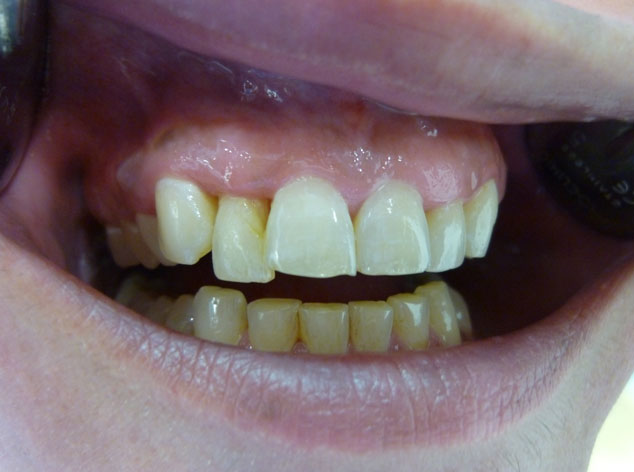

En estos casos han sido tratados con la filosofía de all-at-once, en la

misma sesión: